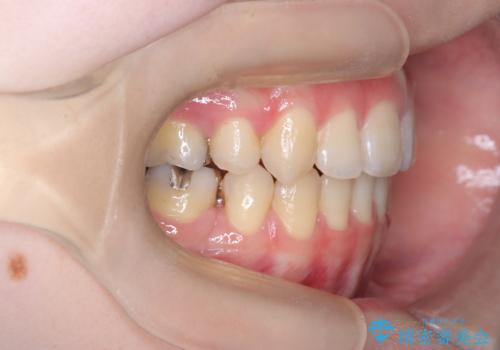

開咬・叢生(八重歯)を抜歯矯正で改善|ワイヤー矯正(クリア装置)症例

- ワイヤー矯正(クリア装置)

- 開咬と歯のデコボコ(叢生)、八重歯を主訴にご来院された患者様です。

矯正の精密検査の結果、上顎左右4番および下顎左右5番の計4本を抜歯し、ワイヤー矯正(クリア装置)にて治療を行いました。